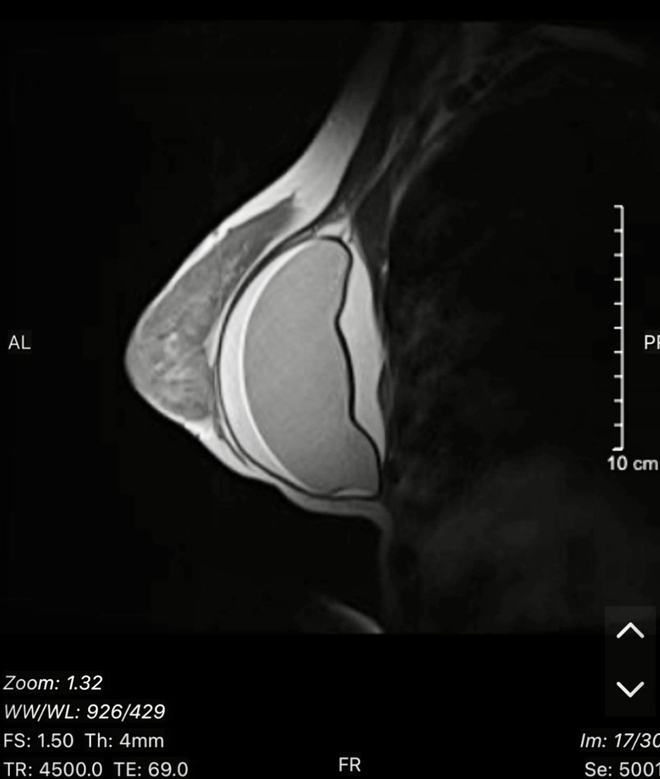

Trải qua quá trình nâng ngực để tạo ra vẻ đẹp hoàn hảo, không ít phụ nữ đã gặp phải tình trạng vỡ túi ngực mà không hề hay biết. Câu chuyện đằng sau những trường hợp này đang gây chú ý lớn trong giới y học và làm đẹp.

Các bác sĩ chuyên khoa phẫu thuật tạo hình thẩm mỹ đã ghi nhận nhiều trường hợp bệnh nhân đến khám mắc phải tình trạng túi ngực vỡ sau quá trình nâng cấp. Điều đặc biệt đáng chú ý là nhiều phụ nữ không nhận ra dấu hiệu này cho đến khi xảy ra sự cố.

Nâng ngực một thời gian, bị vỡ túi ngực mà không hề hay biết - Ảnh 1.